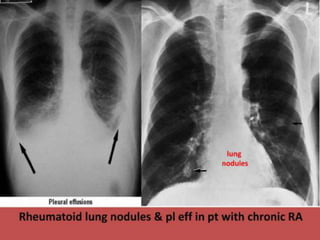

● Pleural effusion